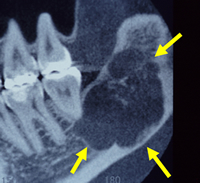

顎骨腫瘍

下顎の中に腫瘍ができ、骨を溶かしています(黄色の矢印)。

全身麻酔下で、腫瘍と一緒に下顎を切除しました。

切除後は腰の骨(腸骨)を移植し、顎を再建しました。

※写真をクリックすると大きい画像が開きます。